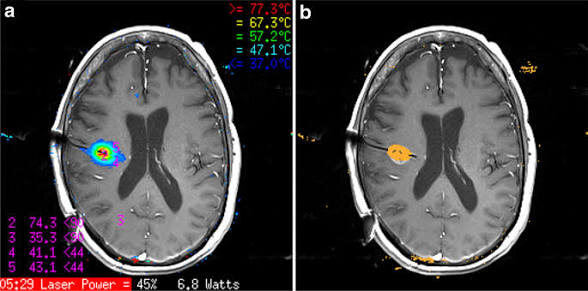

• Ключевая технология: во время абляции МР‑сканер непрерывно конвертирует данные в температурную карту, а ПО рассчитывает «поля термоповреждения/цитотоксичности» (thermal damage threshold, TDT) для управления границами абляции.

• Точность + контроль в реальном времени: МР‑термометрия и TDT‑контуры позволяют сдерживать тепловое поле и снижать риск «лишней» коагуляции окружающих структур по сравнению с «слепыми» методами термодеструкции.